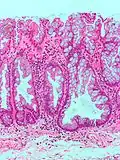

| Hyperplasique | Cryptes dentées non-ramifiées | Non | ![]() |

Hyperplasique polypose syndrome | |